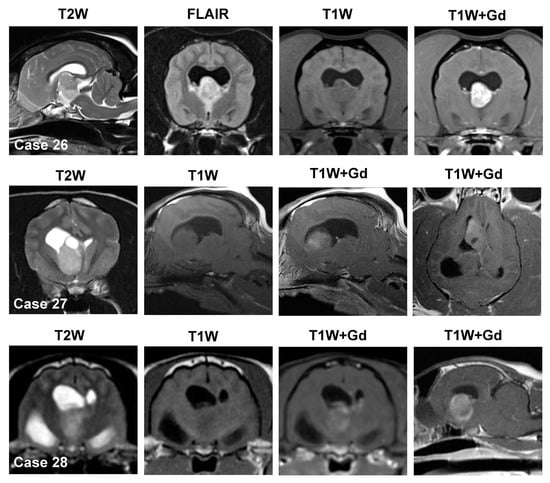

3.4. Solitary Intraventricular Mass Lesions

3.4.1. Choroid Plexus Tumors

3.4.2. Ependymoma